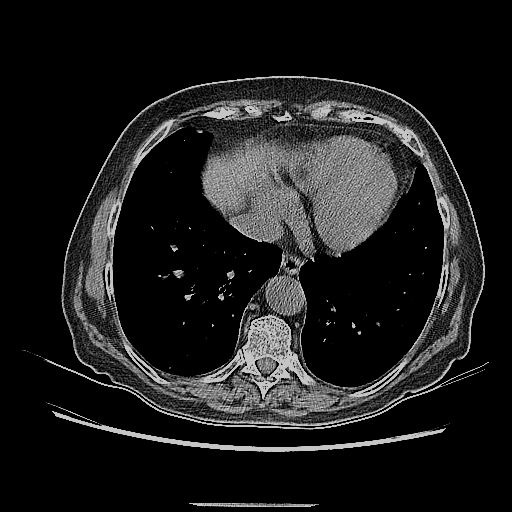

Generated VENOUS CT scan (A→B translation)

Full window (WL 1023.5, WW 4095 β†’ Low βˆ’1024, High +3071)

Lung window (WL -600, WW 1500 β†’ Low βˆ’1350, High +150)

Mediastinum window (WL 40, WW 400 β†’ Low βˆ’160, High +240)